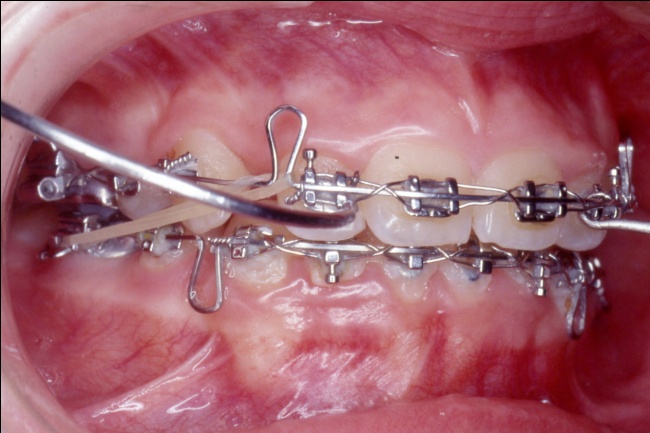

3 - L’art du contrôle en orthodontie

Le traitement a reposé sur des extractions ciblées et une mécanique orthodontique complexe, utilisant la méthode de Tweed avec ancrage maximal pour reculer les dents antérieures sans avancer les dents postérieures. Cette rétraction des blocs incisivo-canins a permis de repositionner les lèvres et d’harmoniser le profil. Un tel contrôle des mouvements dentaires est impossible avec de simples gouttières d’alignement, qui ignorent l’impact sur les tissus mous.